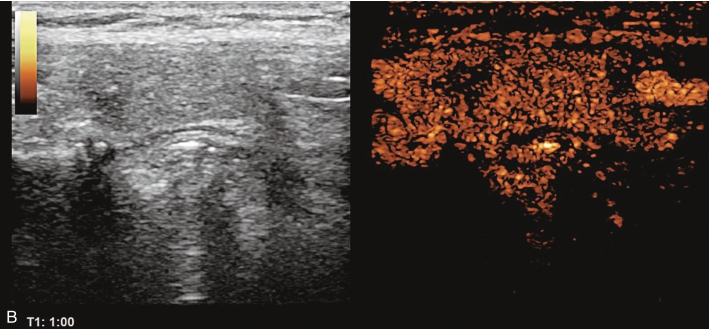

甲状腺右叶上部结节超声造影后早于周围组织开始出现增强,达峰时呈偏低增强表现,边界不清,范围未见明显扩大,之后快速消退,晚期呈明显低增强,结节旁甲状腺被膜增强完整,见图1-9-6、ER1-9-3。

造影后结节内呈不均匀偏低增强表现,增强边界不清,增强晚期快速消退。

图1-9-6 甲状腺髓样癌超声造影图

A.动脉早期;B.达峰时;C.增强晚期

髓样癌体积较小时与乳头状癌的鉴别存在困难,内部丰富血流是髓样癌的主要特点,超声造影表现为中等偏低增强,与乳头状癌明显的低增强表现有别。

常规超声表现类似,超声造影后腺瘤常边界清楚,周边可见规则环状增强。实验室检查中降钙素、CEA升高对于髓样癌的确诊具有重要意义。